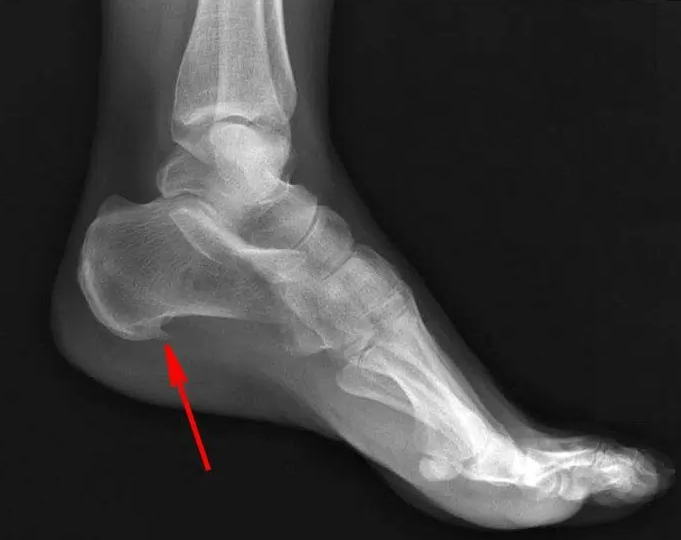

Резкая, сильная боль в пятке, будто гвоздь забили – что такое пяточная шпора и как ее лечить?

Одной из самых неприятных для ног проблем считается паточная шпора. Она возникает в области стопы, внутри пятки, мешая нормальному хождению не то что на каблуках, а вообще в обуви как таковой. Молодые мамы также могут страдать от данной патологии, в виду особенностей изменений организма и метаболизма, поэтому важно знать, что это и каким образом распознать проблему. Что это такое? Шпора пяточная (плантарный фасциит) – это особая патология опорно-двигательного аппарата, которая проявляется болевыми ощущениями в области пятки, вызванными наличием воспалительных и дегенеративных изменений в области подошвенной фасции. Боли возникают в связи с травмированием мягких тканей, которые окружают пяточную кость, и формированием костного разрастания в виде шипа. Обычно шпора пяточная является результатом постоянной физической нагрузки на ноги и область подошвенной фасции, где возникают микроскопические надрывы тканей, которые воспаляются и формируют боли. Пяточная шпора – причины Обычно пяточная

Часто у пожилых мужчин и женщин образуется болезненная шишка на пятке из-за воспаления стопы. Это вызывает боль, которая усиливается при ходьбе. Проблема может появиться из-за плоскостопия, лишнего веса, сахарного диабета, артрита, малой активности, нарушений кровообращения, после травм или инъекций в пятку. Причины возникновения Существуют три типа пяточной шпоры: Симптомы Основной признак — это стартовая боль, проявляющаяся, когда человек встает после долгого сидения или лежания, или утром, делая первые шаги. Боль может быть острой и сосредоточена в пятке, но иногда распространяется на всю ногу. Сначала она сильная, но через 5-10 минут может утихнуть. Иногда в течение дня боль возвращается и становится хуже. Другие симптомы пяточной шпоры включают: Пяточная шпора бывает двух видов: внутренняя и задняя. Внутренняя находится на дне пятки и представляет собой костный нарост. Задняя, или ахиллова, шпора формируется сзади, где крепится сухожилие. Особенности Первая стадия заболевания, или

Откуда берётся пяточная шпора и как вернуть себе лёгкость шага

Представьте: вы встаёте утром с кровати, делаете первый шаг — и резкая, жгучая боль пронзает пятку, будто в неё вонзили раскалённый гвоздь. С каждым шагом всё хуже: невозможно ступить на пятку, приходится перекатываться на носок или хромать. Эта боль может пройти к обеду… но завтра утром вернётся вновь. Так начинается пяточная шпора — состояние, с которым сталкиваются миллионы людей, особенно после 40 лет. Многие думают, что шпора — это костный «нарост», который «врастает» в мягкие ткани и вызывает боль. Но на самом деле всё сложнее — и одновременно проще. Боль возникает не из-за самой шпоры, а из-за воспаления, которое её сопровождает. А значит — с ней можно справиться. Даже без операции. Давайте разберёмся, что на самом деле происходит в пятке, почему это случается именно с вами, и какие проверенные методы помогают вернуть лёгкость шага — без боли, без страха и без лишних расходов. Что такое пяточная шпора — на самом деле? Пяточная шпора — это кальциевое уплотнение (остеофит), кото